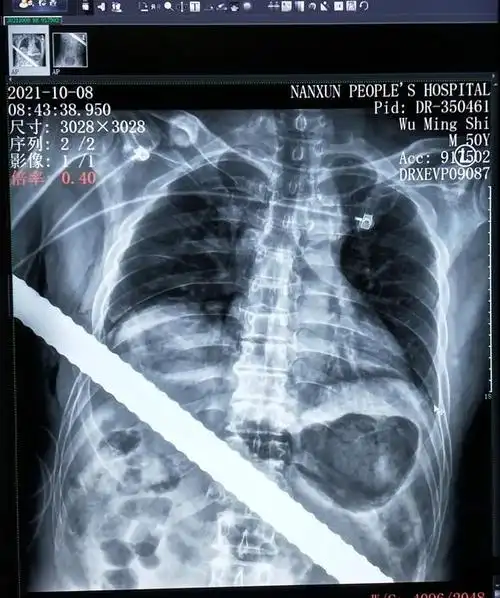

惊心动魄2小时!湖州男子被1米长钢筋刺穿胸腹